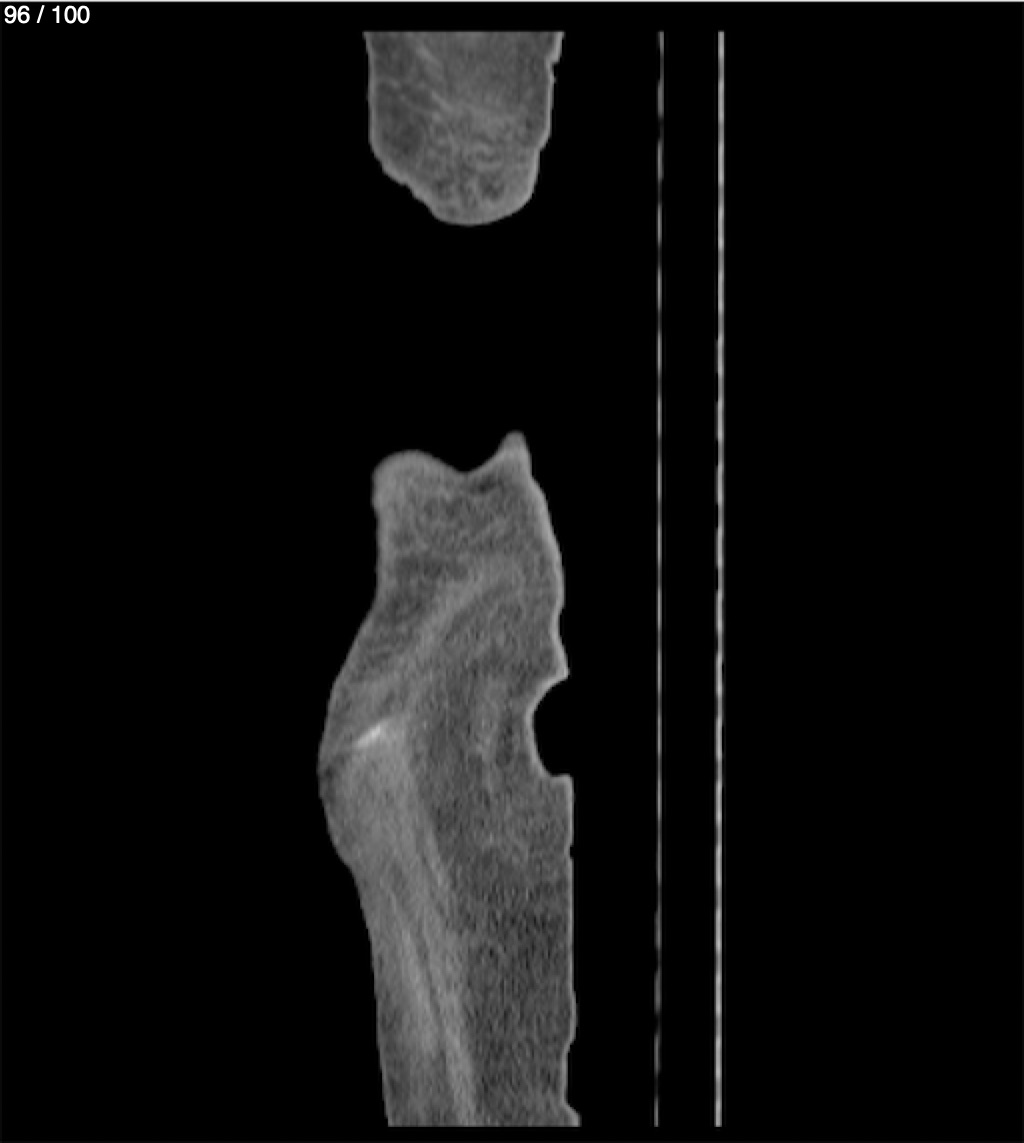

Hilda Geronimo Mendez 60A - T.C Abdomen Simple